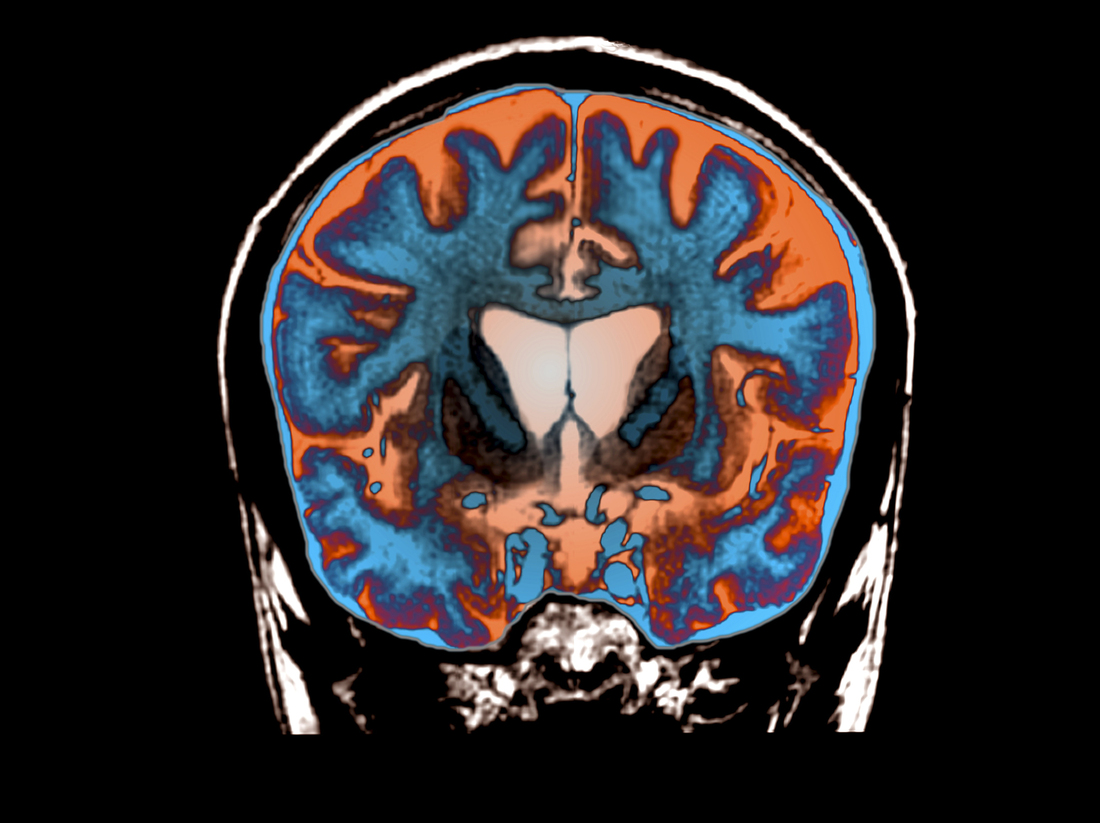

An MRI scan shows signs of atrophy in the brain of a patient with Huntington’s disease.

Science Photo Library/Science Source